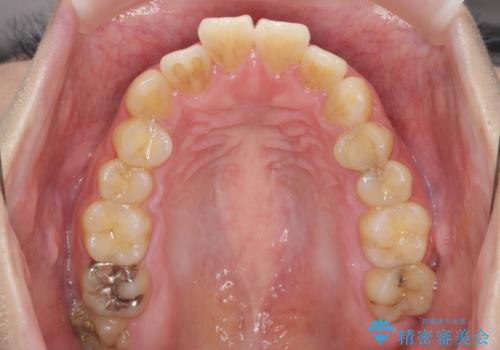

歯を抜かずに行う前歯の角度の改善

- 歯を抜かずに前歯の角度を改善したい、と矯正治療を希望され来院されました。

可及的に前歯部にIPR(歯間の削合)を行い、抜歯をせずマウスピース矯正システムインビザラインで歯の排列を行っていく治療計画としました。

治療の前後を比べると、がたつきや歯の角度が改善したことがしっかりと確認されました。